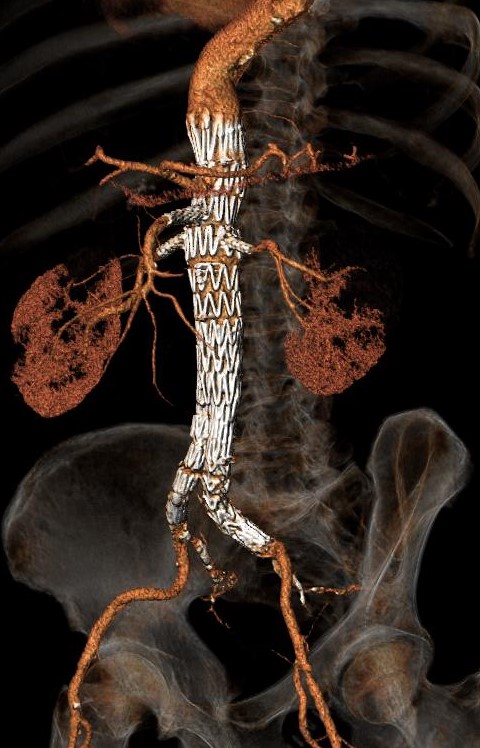

Επιπρόσθετο ανώνυμο φωτογραφικό υλικό

από την αντιμετώπιση ανευρυσμάτων της κοιλιακής αορτής και των λαγονίων αρτηριών

από το προσωπικό μου αρχείο στα Πανεπιστημιακά Νοσοκομεία Λάρισας και Ιωαννίνων

• Περιπτώσεις ανευρυσμάτων κοιλιακής αορτής

• Περιπτώσεις πολύπλοκων ανευρυσμάτων κοιλιακής αορτής